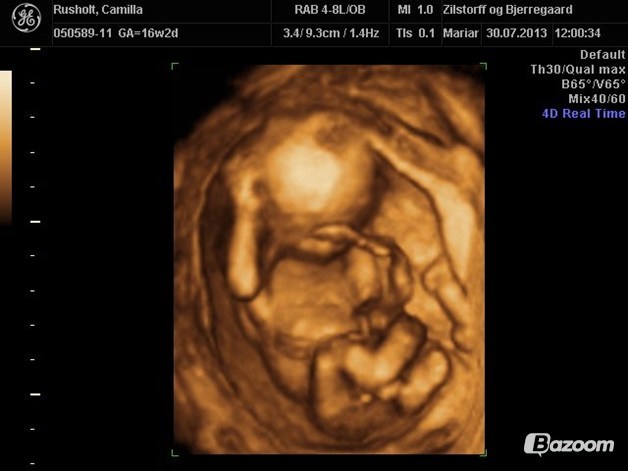

Vi var til kønsscanning i uge 16, hvori der også var lidt 3D

Vedhæftede fotos (klik for at se i fuld størrelse)

Dejligt og se de skønne billeder

Jeg har nemlig selv bestilt en kønsscanning i uge 16, så ville lige se om man overhovedet kan se noget der.

Og det kan man jo